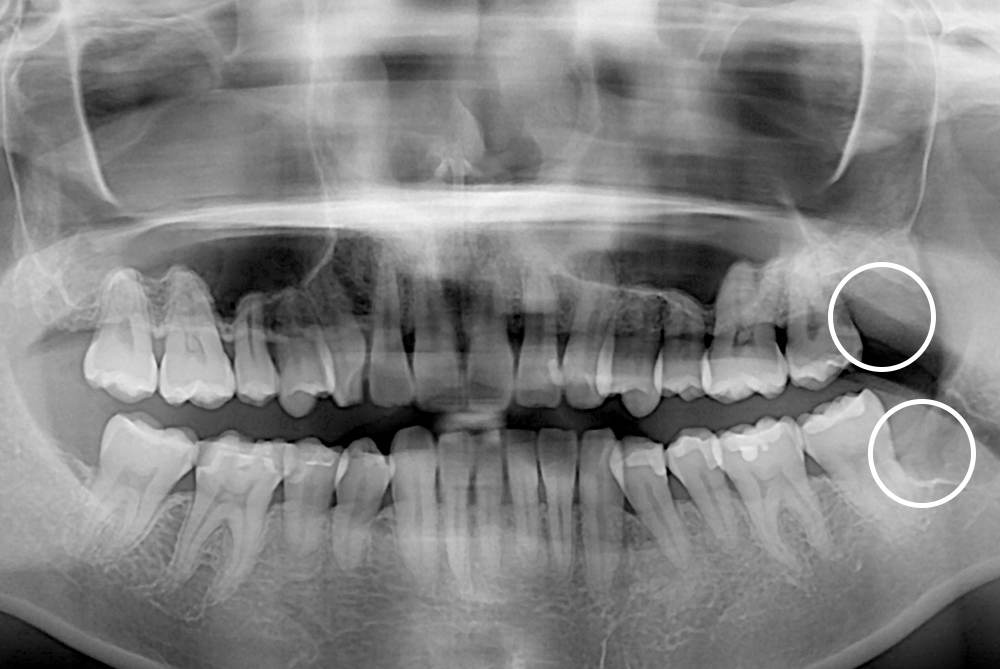

[사랑니] 매복 사랑니 발치

치료후 : 2018-04-30

세종치과는 구강악안면외과학 박사이신 원장님이 발치하는 치과입니다.